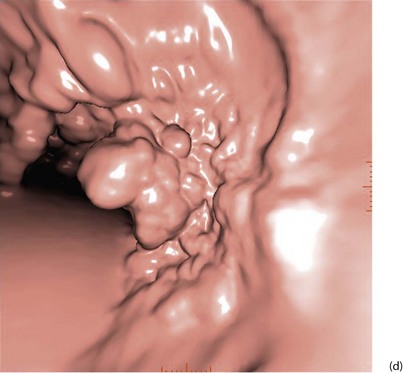

With improved technology, CT is increasingly used for large bowel examination. It can be performed without laxative preparation where it would be acceptable to miss small polyps, for example in suspected obstructing lesions. CT can be useful in the frail elderly when a right-sided colonic cancer is suspected because of anaemia or a palpable mass. For a more complete examination, CT colonography (also known as CT coloscopy or virtual colonoscopy) requires full bowel cleansing. During the procedure, air or carbon dioxide is insufflated into the colon; the technique is sensitive enough to detect lesions larger than 1 cm. The investigation is quicker and less unpleasant than barium enema and has replaced it altogether in some units. Hundreds of images are produced and the best are viewed on workstations along with reconstructed axial and 3D images of the bowel lumen (see Fig. 5.5).